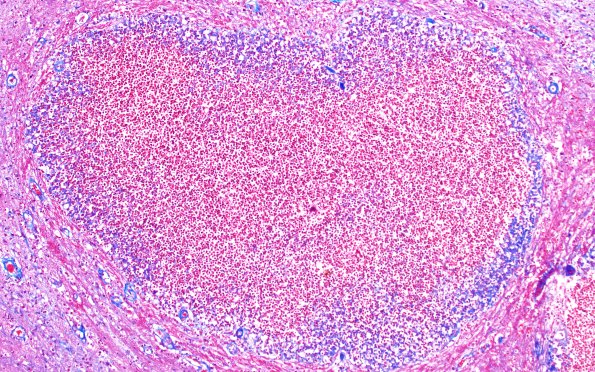

Washington University Experience | INFECTION | Bacteria | Abscess | Abscess, Subacute - Chronic | 17F6 Abscess B (Case 17) N12 TRI 10X

The small abscesses of image initially shown as image #16C9 demonstrate a thin collagenous capsule. (Trichrome)